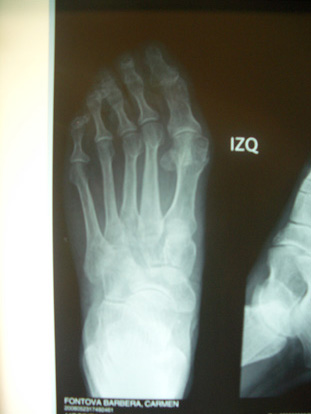

Radiografia pre-operatòria